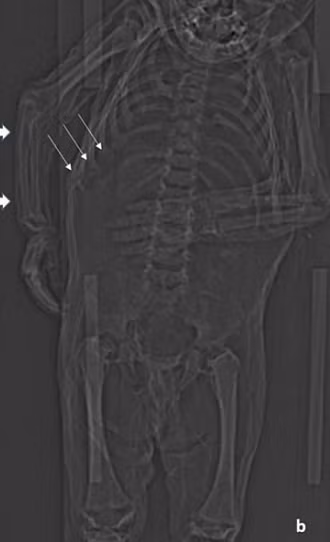

Các nhà nghiên cứu từ Phòng thí nghiệm Munich-Bogenhausen của Đức xác định rằng, cậu bé có khả năng mang tên là Reichard Wilhelm và đã chết vào năm 1625 hoặc 1626, cách đây khoảng 4 thế kỷ. Cơ thể của cậu bé được bảo quản khá tốt bằng phương pháp ướp xác. Điều này cho phép các nhà nghiên cứu có thể phân tích mô mềm của xác ướp bằng cách sử dụng máy quét CT.

Các nhà khoa học cũng đã nghiên cứu răng cũng như đo xương của đứa trẻ. Kết quả cho thấy em bé này từ 12 - 18 tháng tuổi khi qua đời. Cậu bé có mái tóc đen và thừa cân so với tuổi của mình, cho thấy cậu đã được ăn uống và chăm sóc đầy đủ.

Tuy nhiên, kết quả chụp CT thể hiện xương sườn của cậu bị biến dạng, dấu hiệu của căn bệnh chuyển hóa xương (Metabolic Bone Disease - MBD) thường được thấy trong các trường hợp mắc bệnh còi xương nghiêm trọng. Hình ảnh chụp cắt lớp cũng cho thấy tình trạng đặc trưng của bệnh viêm phổi.